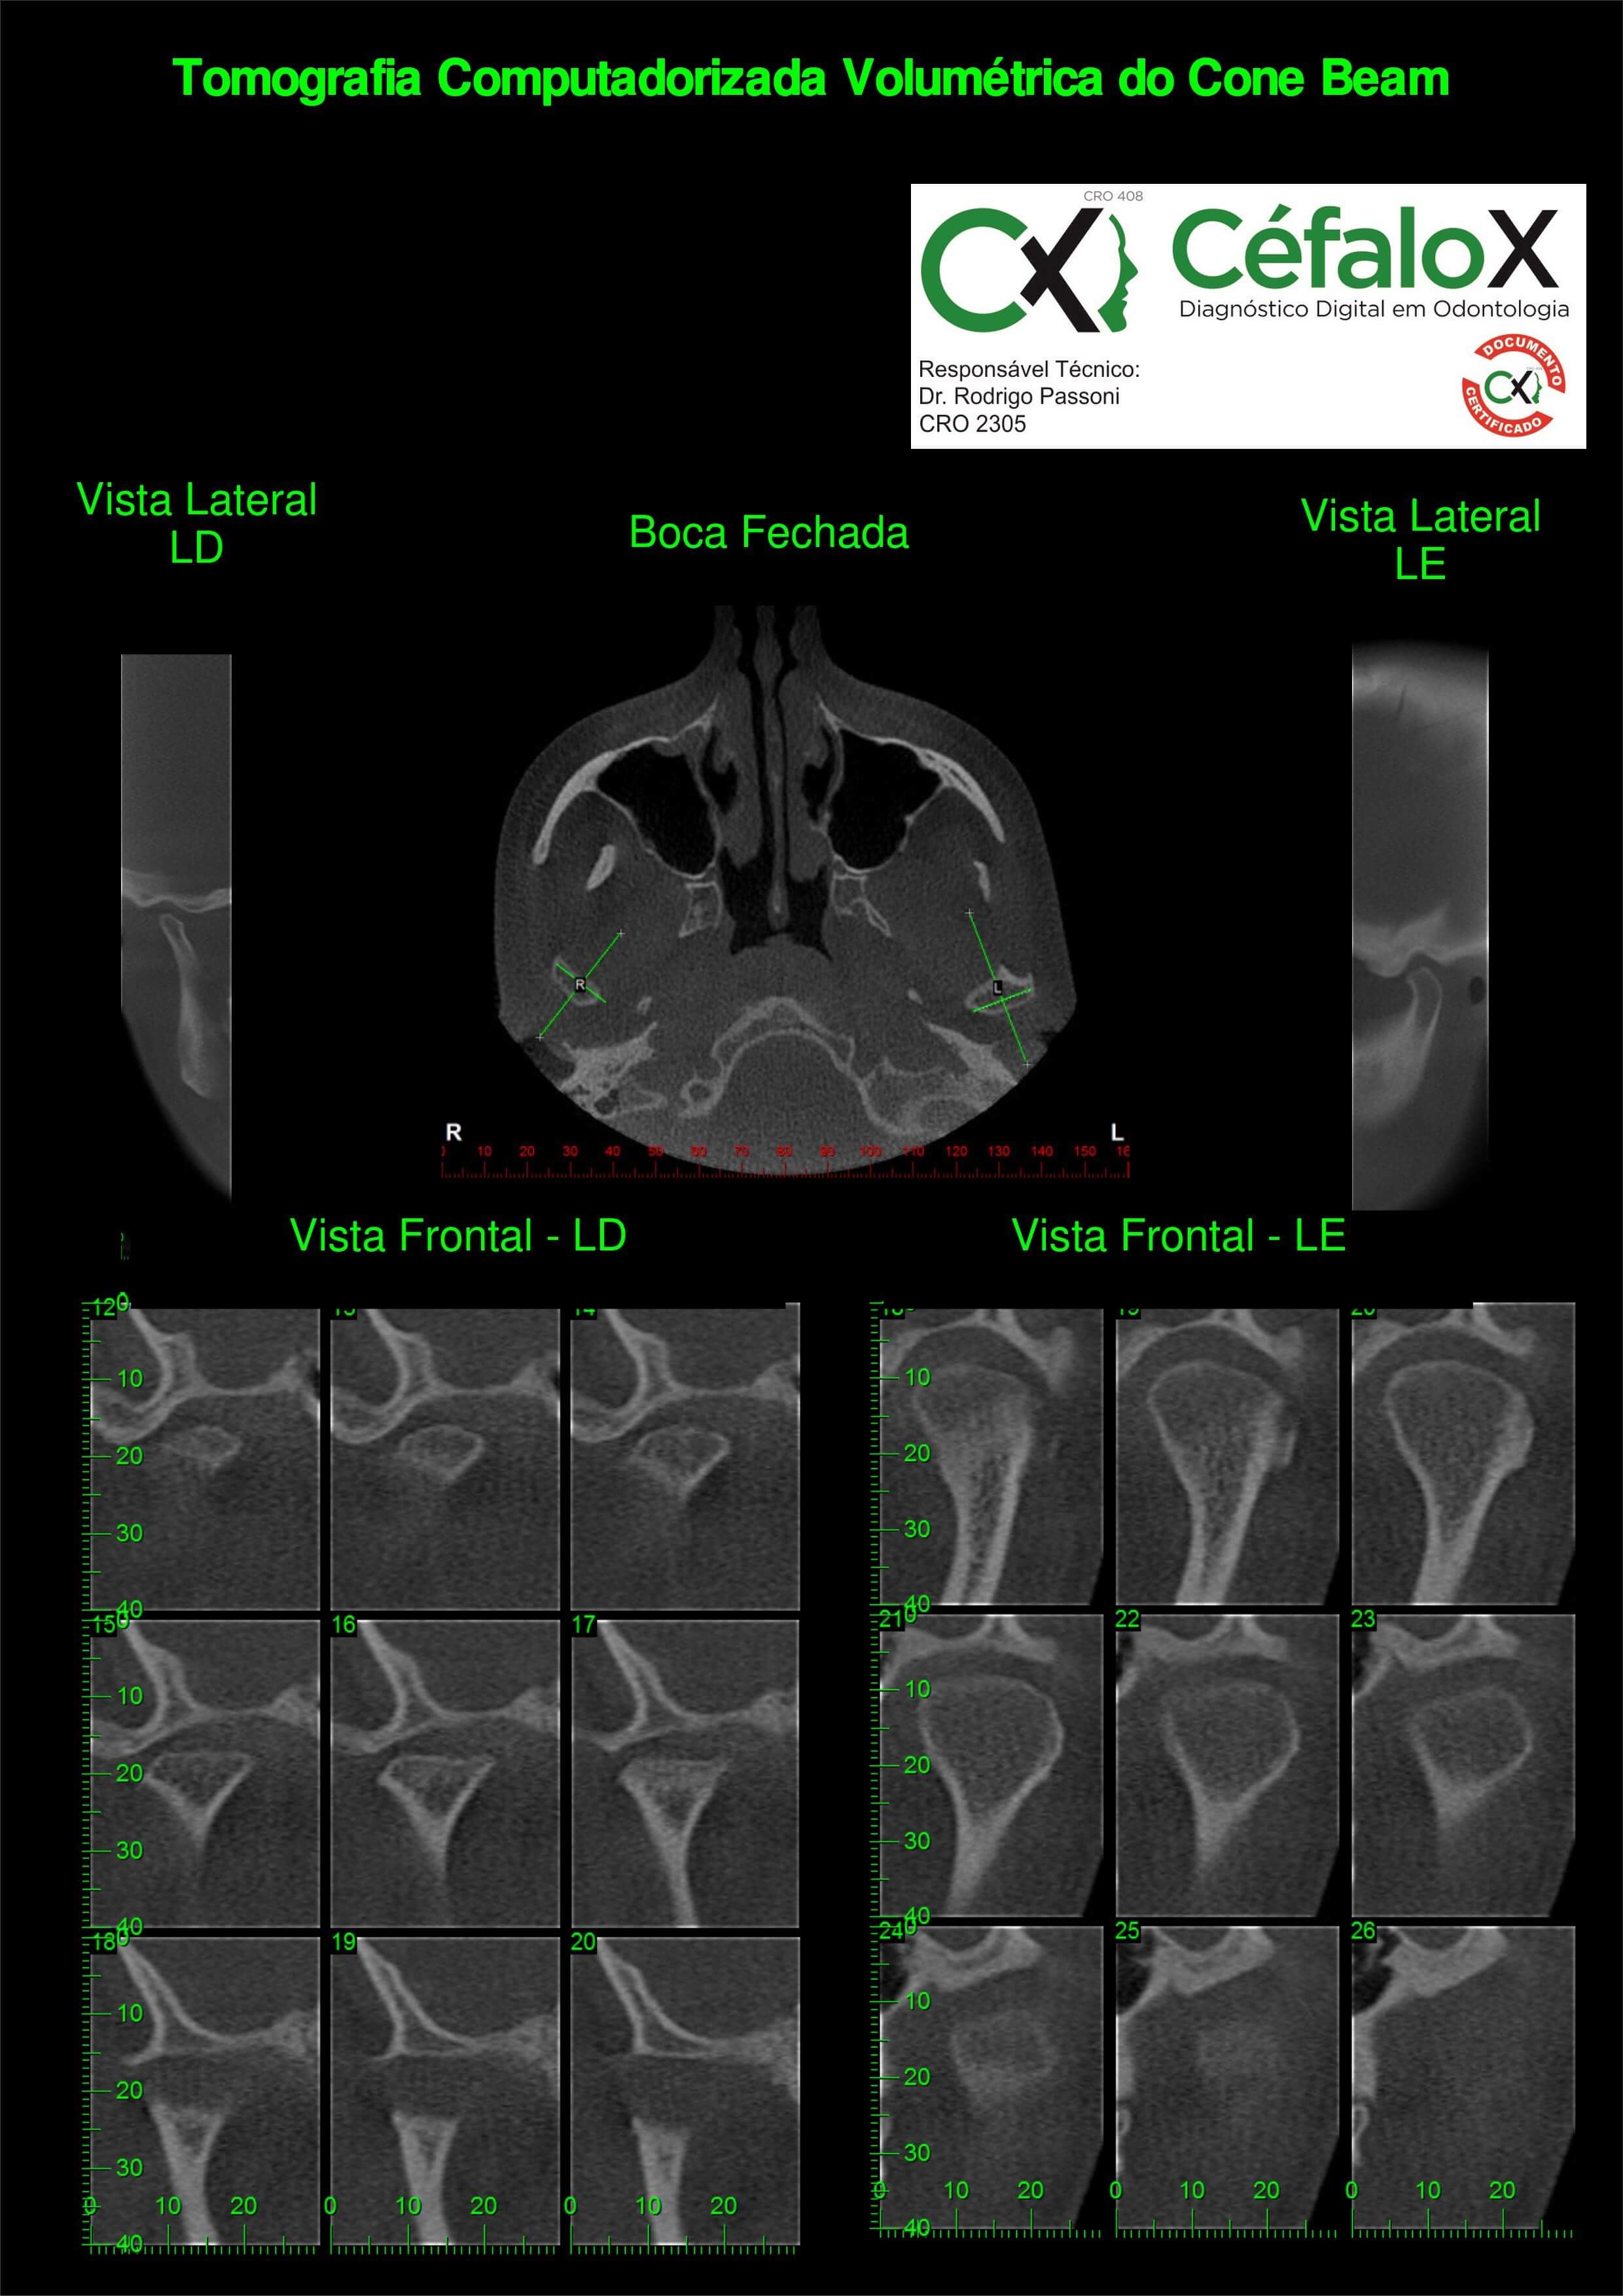

TC de face (do Hióide à Glabela), reconstruções 3D do tecido mole/ósseo/vias aéreas, radiografia panorâmica, telerradiografia lateral e frontal com traçado, cortes transversais e axial de maxila/mandíbula, ATM e arquivo DICOM – entregue em pasta e caixa de Pvc.